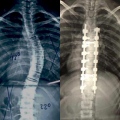

Fotos